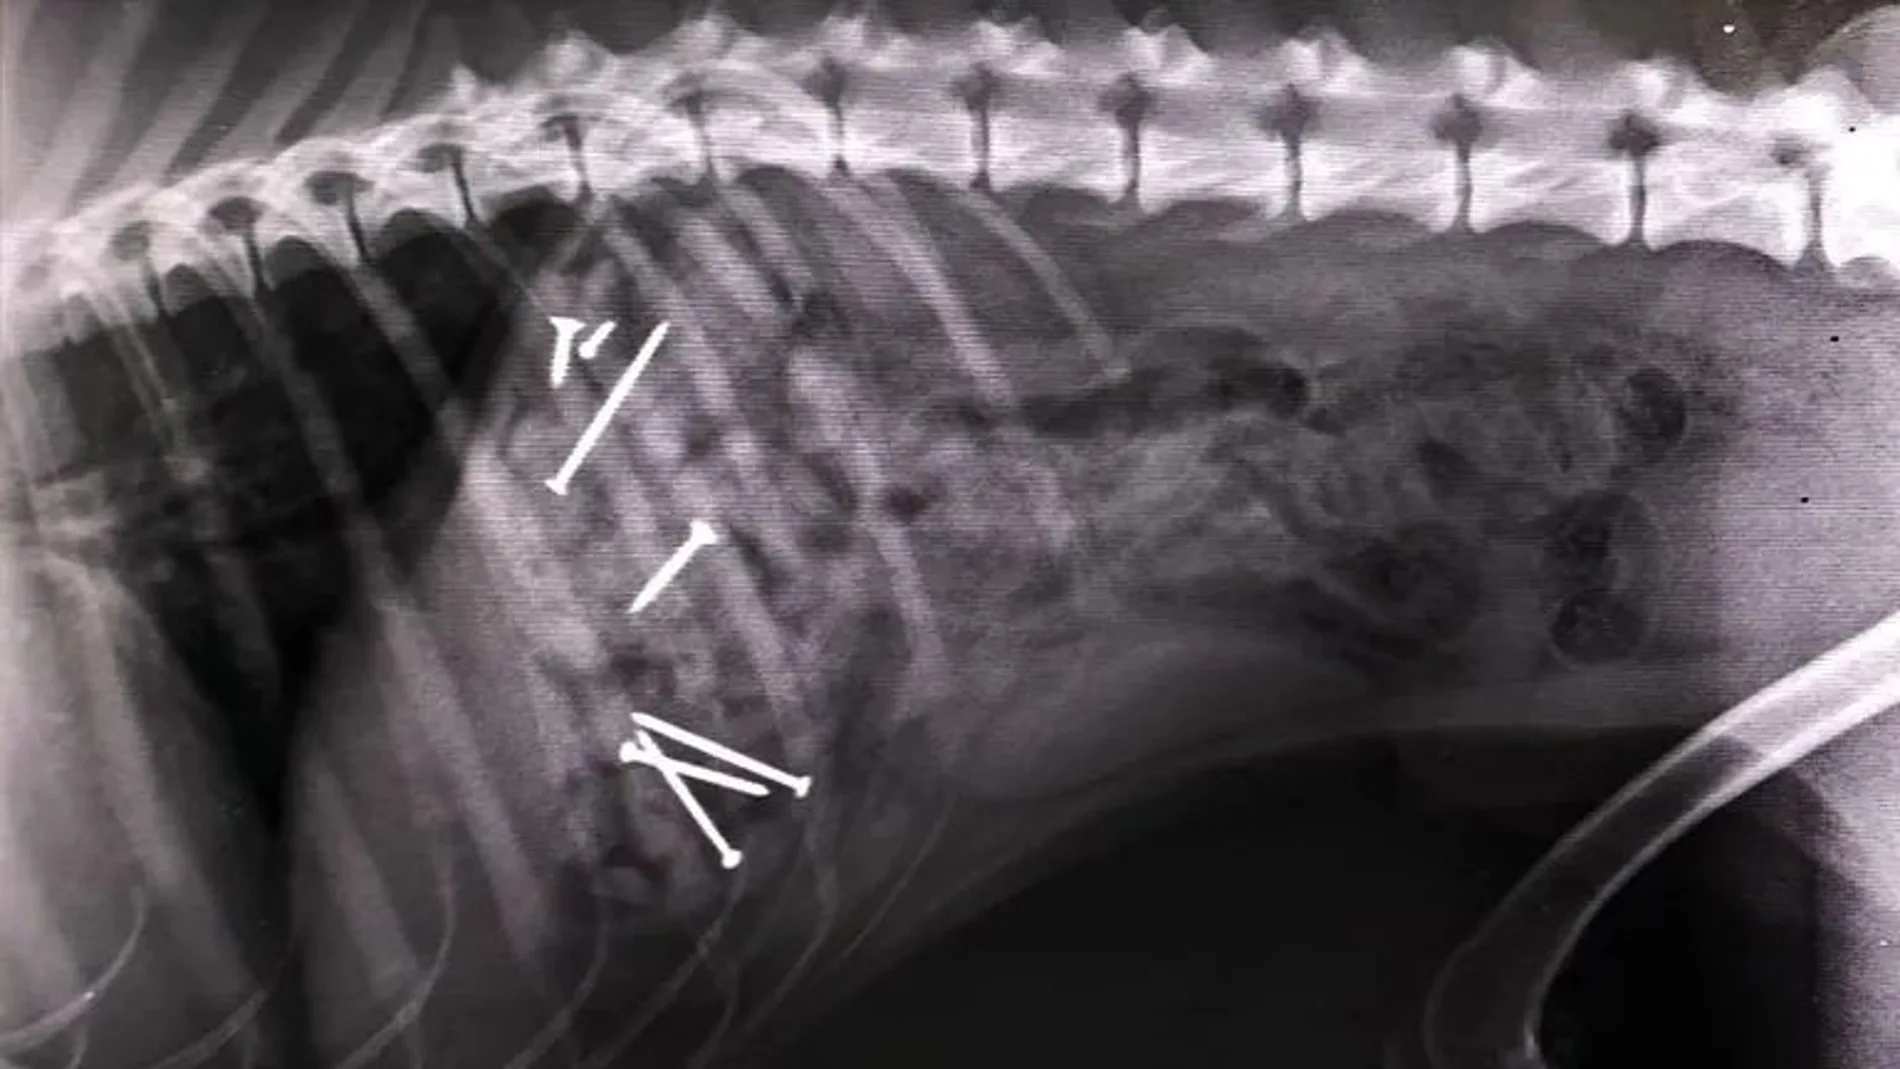

En la primera de las ubicaciones se han encontrado salchichas con clavos en su interior. Las esconden entre las hojas y el olor atrae a los perros. Cuando el animal ingiere la comida, es básico llevarlo a un veterinario para que pueda operar al can y evitar, así, la muerte. Pero no es el único cebo que se ha encontrado en los últimos días. En el Arenal la trampa va más allá.